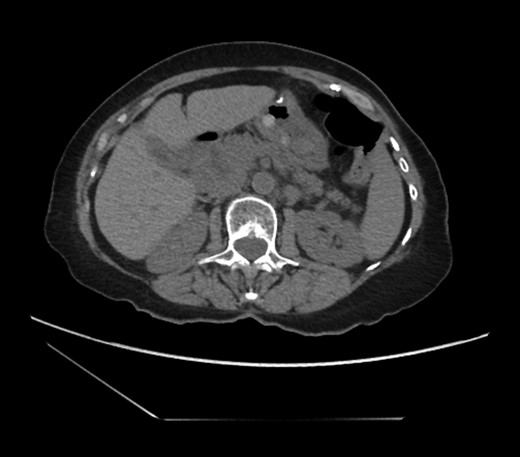

An 81-year-old female with a medical history of CAD with stents, hyperlipidemia, hypothyroidism, GERD, recent UTI, pancreatic cyst, constipation, anemia and leukopenia presented to the ED with a 1 day history of mild, diffuse and cramping abdominal pain. The patient was unable to give an accurate history, but the son at bedside supplemented this reporting that for several years the patient had been experiencing ill-defined abdominal discomfort. Physical exam showed a soft abdomen with mild tenderness and no evidence of peritonitis. A CT scan of the abdomen and pelvis with IV and PO contrast (Fig. 1) showed edematous changes to the mesentery of the small and large bowel with swirling of vessels indicative of internal hernia. The stomach was also noted to be distended with both air and fluid as a consequence of posterior compression by the hernia contents (Fig. 2). A surgical consult was obtained, a nasogastric tube and Foley catheter were placed, antibiotics were started, and the patient was taken for an exploratory laparotomy. Upon entering the abdomen through a vertical midline incision, 1.5 l of ascites was drained revealing a diffusely edematous mesentery. A large portion of the small bowel was seen to be herniated through the Foramen of Winslow (Fig. 3). A Kocher maneuver and division of the gastrocolic ligament were then performed to allow release of the herniated small bowel. It was at this time that, in addition to small bowel, a large portion of the ascending and transverse colon was noted to be herniated through the foramen of Winslow. The small bowel was also seen to be torsed about its own mesentery. Normal anatomy was restored and the bowel noted to be healthy and viable with peristalsis (Fig. 4). Due to the large size of the foramen after reduction and enlargement, it was deemed best to leave it open to prevent any further incarceration or strangulation. The abdomen was closed and the patient tolerated the procedure well. At a follow-up visit 2 months later, the patient had well-healed incisions, was doing well, tolerating a diet, and gaining weight appropriately.

Loops of bowel between IVC, liver, and lesser curvature of the stomach. Arrow small bowel. Arrow head stomach.

Diagnosing an internal hernia is frequently accomplished using physical exam and CT imaging. Abdominal X-ray does have some nonspecific findings suggestive of internal hernia but is usually inadequate for diagnosis. Diagnosis of a foramen of Winslow hernia, however, is only accomplished in 10% of patients preoperatively [3]. As previously mentioned this diagnosis is rare and often presents with vague obstructive type symptoms. This likely contributes to the low occurrence of accurate preoperative diagnosis. However, several radiographic findings were seen in this patient that suggested a foramen of Winslow hernia preoperatively. First, there is visible swirling of the mesentery on the CT scan that is indicative of internal hernia (Fig. 1). Second, there are loops of small bowel that can be visualized between the IVC and the edge of the liver in a supra renal position along the lesser curvature of the stomach (Figs 1 and 2). When compared to a CT of the abdomen and pelvis obtained 4 years prior to presentation, there is actually evidence that this patient had a non-obstructing foramen of Winslow hernia at that time as demonstrated by bowel being visualized in the lesser sack (Fig. 5). These findings, especially small bowel along the lesser curvature of the stomach, are inconsistent with normal anatomy and strongly indicative a foramen of Winslow hernia.